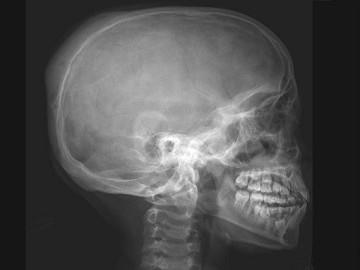

问题 女,12岁,脊柱侧弯畸形,双下肢长短不一,请结合影像图像,最可能的诊断是 ( )

选项 A、非骨化性纤维瘤 B、Paget病 C、骨巨细胞瘤 D、内生软骨瘤 E、骨纤维异常增殖症

答案 E